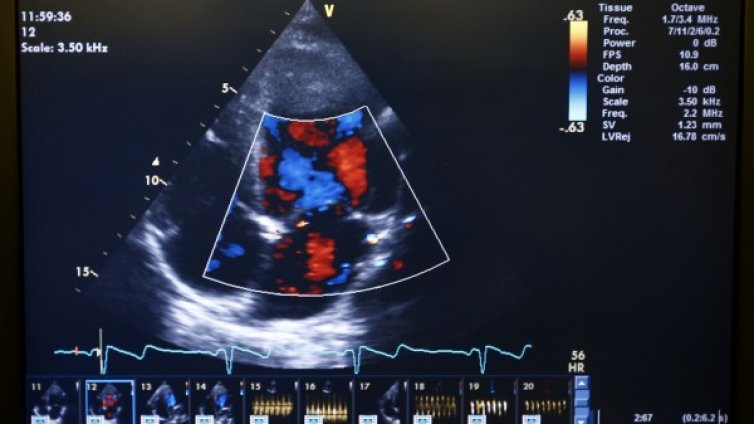

„Хъбъл“ засне рояк от галактики  Мъж, изпаднал в клинична смърт, разказва за срещата си с Бог в рая

Мъж, изпаднал в клинична смърт, разказва за срещата си с Бог в рая  Учени дават обяснение на странен шум, който милиони хора по света чуват късно вечер